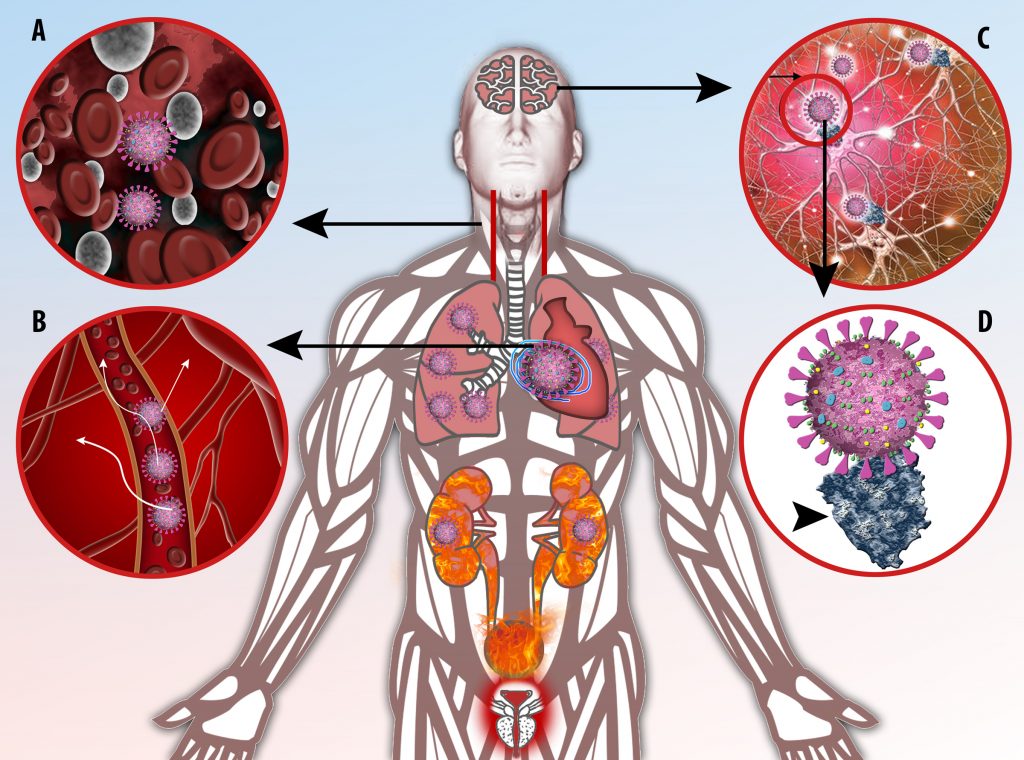

The vast majority of patients with COVID-19 have had a good prognosis, but there are still some critical individuals and even death.10 Most of these critically ill and dead patients do not develop severe clinical manifestations in the early stages of the disease. Some patients only show mild fever, cough, or muscle soreness. These conditions suddenly deteriorate in the later stages of the disease or in the recovery process . Acute respiratory distress syndrome (ARDS) and multiple-organ failure occur rapidly, resulting in death within a short time. Cytokine storm is considered to be one of the major causes of ARDS and multiple organ failure.

This activation induces inflammatory monocytes to highly express IL-6, starting a localized and then systemic cascade effect that results in hyperproduction of IL-6, which accelerates the inflammatory process. Because IL-6 also increases vascular permeability, excessive levels cause blood vessels to become very leaky. This, along with clotting factors released from vascular endothelial cells, stimulates the coagulation cascade, resulting in microthrombosis (tiny clots), which leads to ischemia and tissue death of the kidney, intestines, heart, liver, brain and extremities.